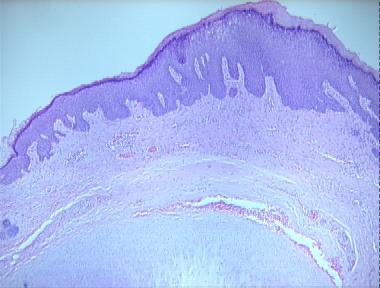

chondrodermatitis helicis nodularis

Histologic Features